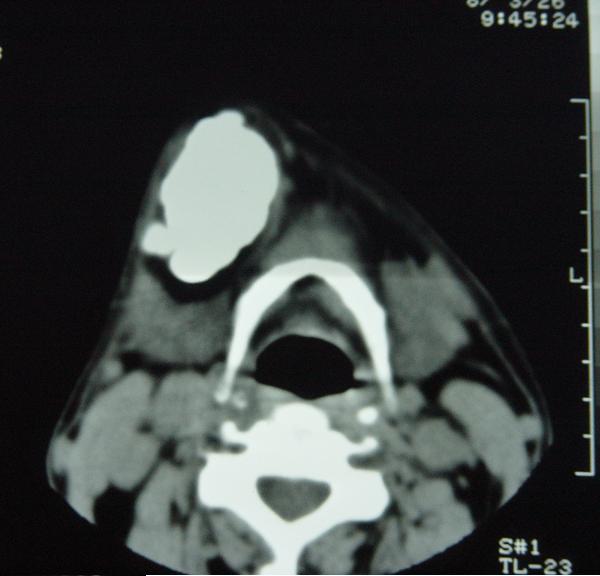

标题: CT12465:下颌骨肿瘤,请会诊 [打印本页]

标题: CT12465:下颌骨肿瘤,请会诊

发现下颌骨肿瘤近30年.逐渐增大.

考虑右侧下颌骨水平部及升部骨纤维异常增殖症可能性大。

考虑右侧下颌骨骨化性纤维瘤。